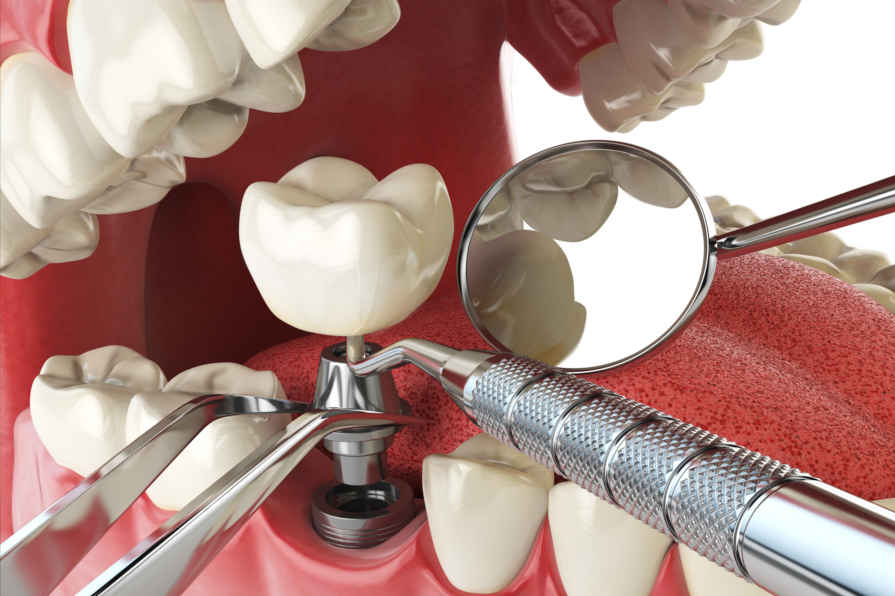

Inplantea

Esperientzia, teknologia eta kalitatea.

- Materi Biokonpatiblea

- 20 urteko baino gehiagoko esperientzia

- BTI inplanteak